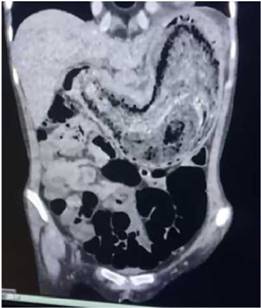

Indagando a la progenitora, esta relata que desde hace dos años la paciente presenta cambios de conducta caracterizado por rasgo esquizoide, sugestivo de patología psiquiatrica4. Al examen físico, paciente en regular estado general, peso 43kg, talla de 173cm y un IMC 15. Cardiopulmonar estable, abdomen: plano, RHA(+), se palpa masa a nivel de epigastrio, no doloroso a la palpación. A su ingreso se le realizo laboratorios que reportaron: Albumina 2.7 gr/dl, proteínas totales 4,6 gr/dl, glicemia 68, glóbulos blancos 6820, glóbulos rojos 4350000, hemoglobina 9,3g/dl, VCM 63,5fL, Hematocrito 27,6. Tomografía abdominal donde se evidencia imagen en miga de pan que ocupa casi en su totalidad la luz gástrica hasta la 3ra porción del duodeno. E ingresa al servicio de cirugía con los diagnósticos: tricobezoar gigante, anemia moderada y desnutrición. Durante su internación se le realizo, como indican las diferentes publicaciones, una endoscopia digestiva alta que reporta: tricobezoar gigante, lesión elevada de duodeno a descartar neo (histopatología reporto, cambios hiperplásicos, signos de ulceración y cambios inflamatorios) y se le indico nutrición parenteral, antibióticos, transfusión de 2 concentrado de glóbulos rojos y valoración por hematología y psiquiatría, este último para realizar un manejo más integral del paciente5. Hematología le diagnostica anemia ferropénica severa, e indica hierro sacarato y psiquiatría diagnostica tricotilomanía y síndrome ansioso depresivo e indica alprazolam. Al séptimo día de internación una vez mejoradas las condiciones generales de la paciente, se decide su intervención quirúrgica, se realiza una laparotomía exploradora, gastrotomía, extracción de tricobezoar y rafia de ulcera gástrica, gastrorrafía y lavado y drenaje de cavidad y como hallazgo transquirurgico además del tricobezoar gastroduodenal se evidencia una ulcera en la cara posterior del cuerpo gástrico. Se decide la conducta precisamente por ser un tricobezoar gigante, que no sería resuelto por endoscopia, además se podría dar solución a la ulcera gástrica en la laparatomia; al ser un cirugía limpia - contaminada y por el tamaño de pieza que se iba a extraer se opto por la vía convencional.